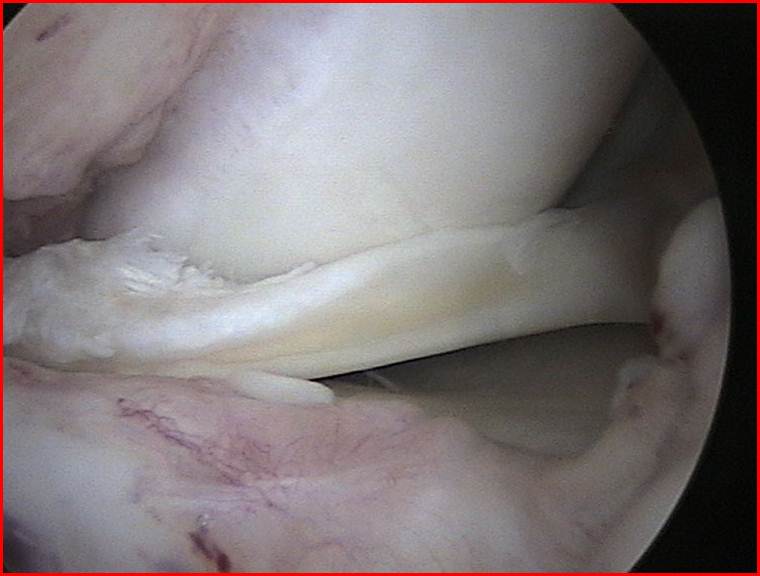

- Lesiones meniscales

- Plástias de ligamentos cruzados

- Lesiones cartílago articular